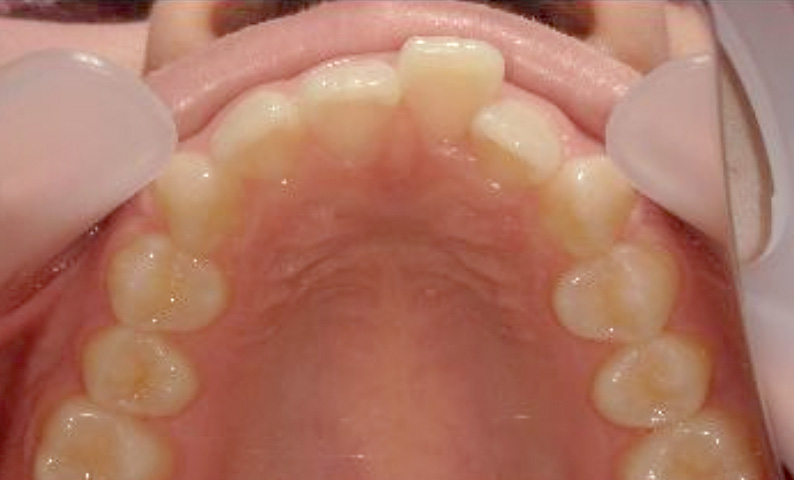

症例_004 上下顎の部分矯正

治療期間:8ヶ月金額:54万円+税女性前歯のガタガタ捻転歯